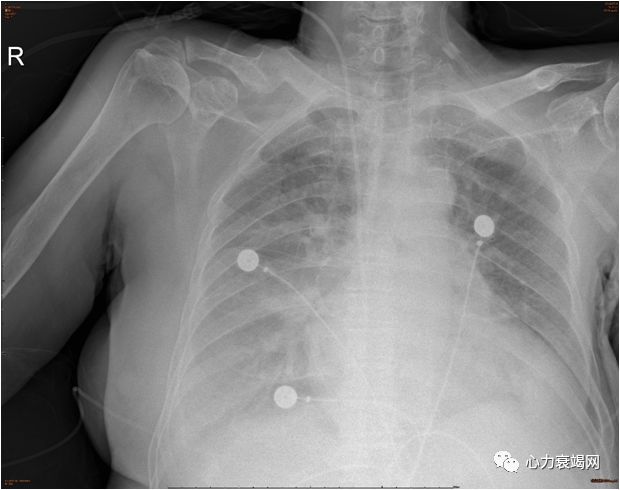

胸 片

两肺渗出,两侧胸腔积液,心影增大,两肺门增大